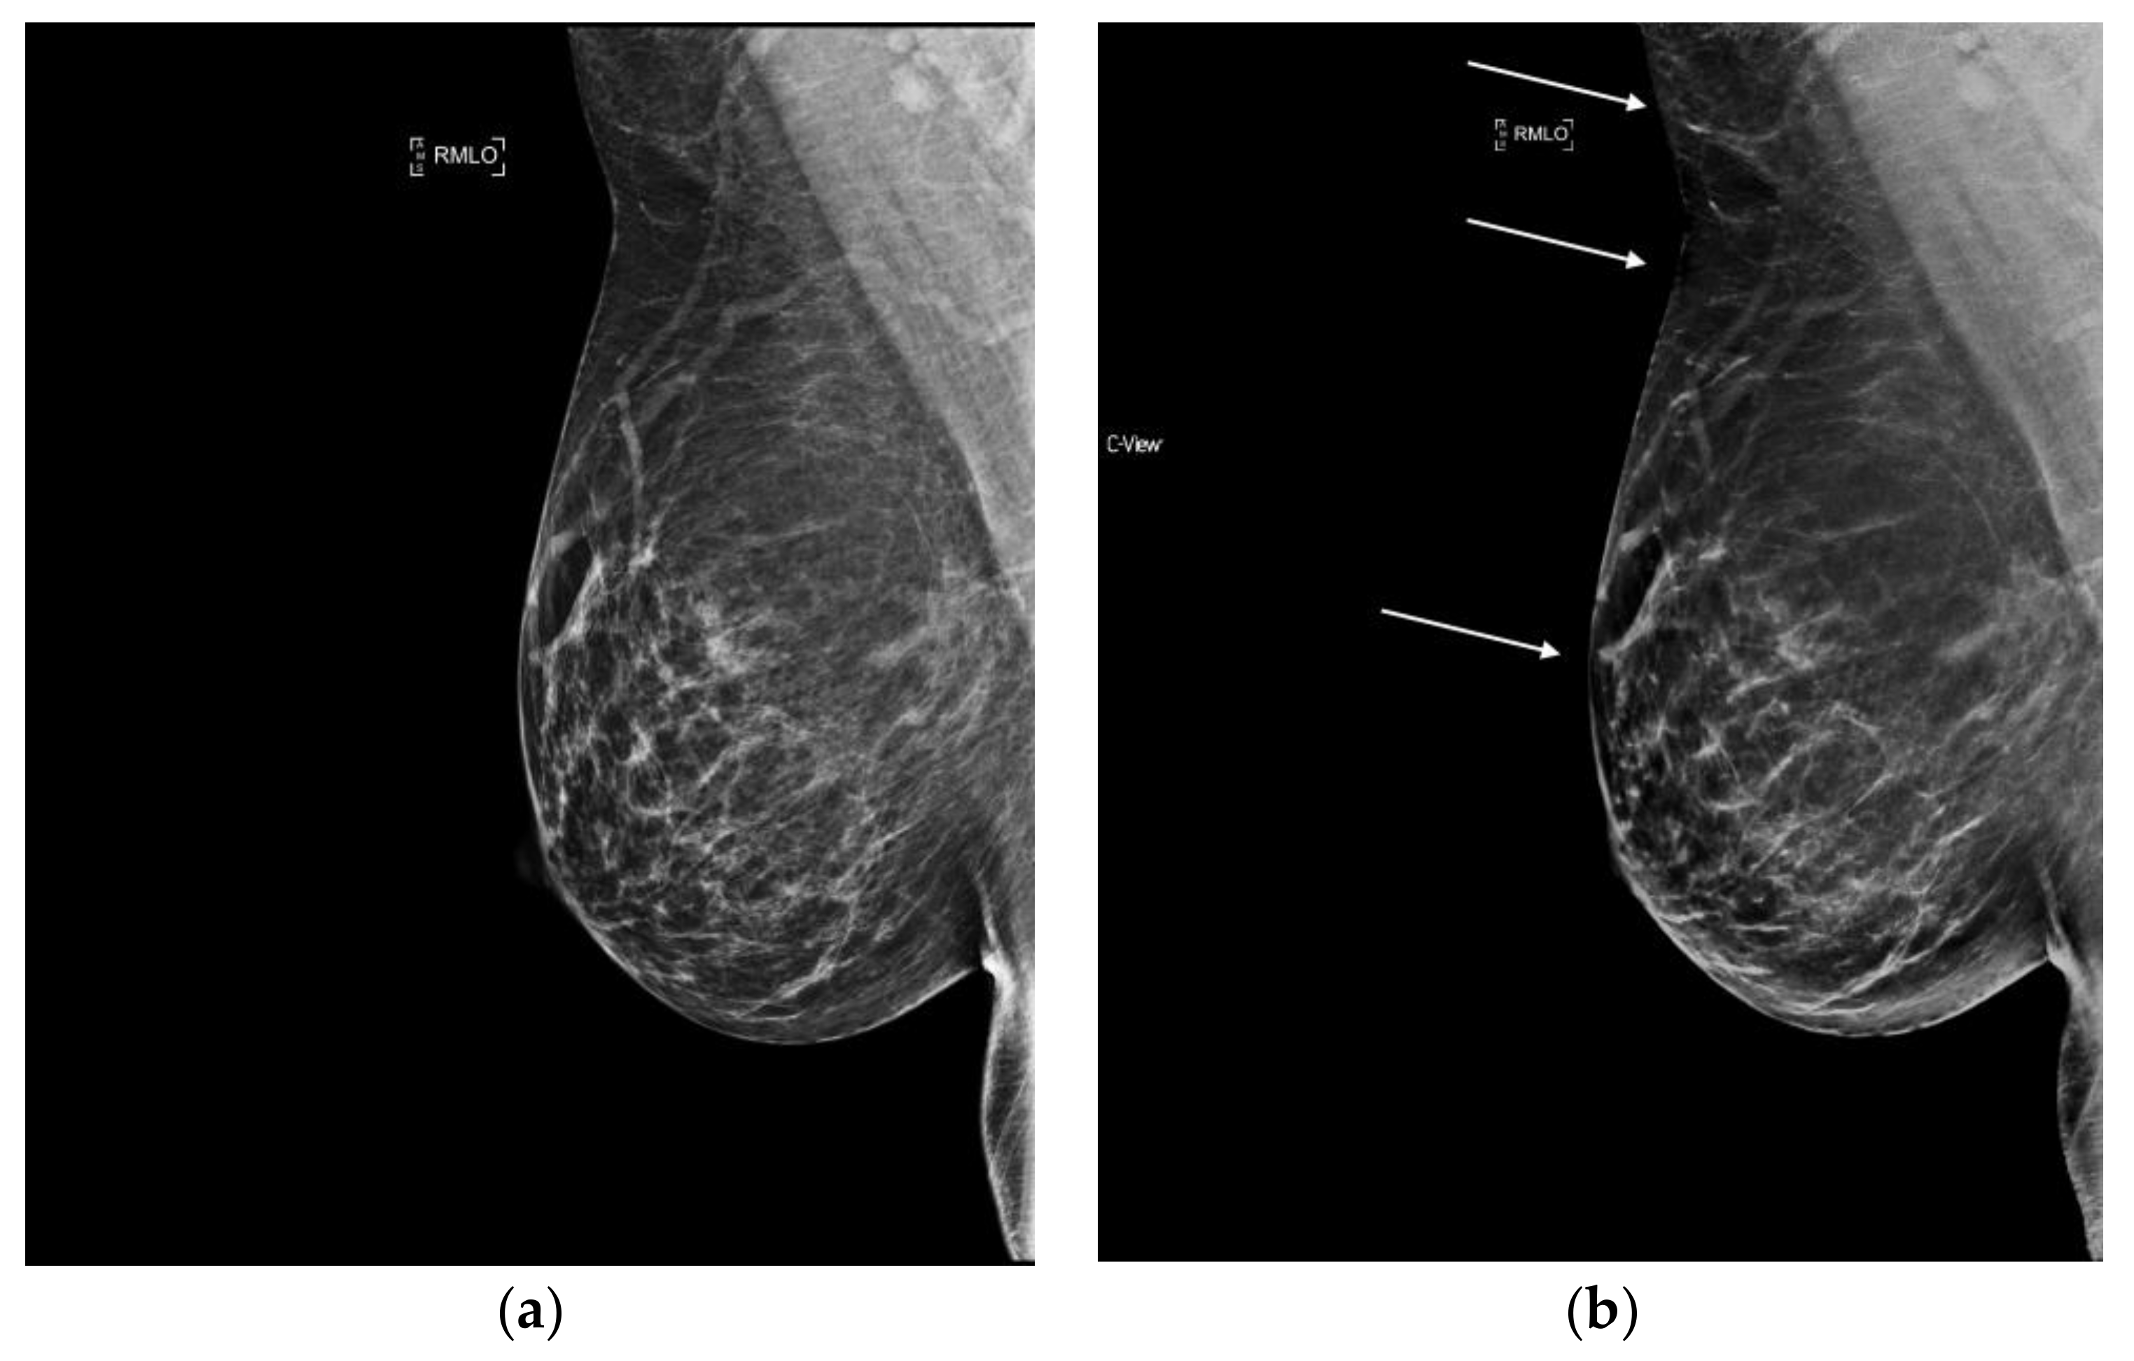

6.4. Masses and Asymmetries

With 2D FFDM, overlapping tissue may obscure the margins of masses and create asymmetrical areas of tissue. One of the benefits of tomosynthesis is the improvement in margin analysis of masses as this tissue is cleared away. This information is passed onto the synthesized image as it is created from the DBT data set, which can lead to clearer conspicuity of masses and their margins (Figure 4). Potentially false positive asymmetries can also be resolved on tomosynthesis. Since s2D is always read in conjunction with DBT, these benefits remain when synthesized mammography is used. (Figure 5).

Figure 4.

Mass, readily detected on synthesized mammography, with clear depiction of spiculated margin. Invasive ductal carcinoma, moderately differentiated, ER/PR+, Her2−. (a) s2D RCC mass (b) s2D RCC zoom.

Figure 5.

Indeterminate asymmetry seen on 2D FFDM is less prominent on synthesized mammography and resolved on DBT slices; no recall was necessary. (a) 2D FFDM (b) s2D.

When stratified by mammographic finding, recall rates were shown to be lower with s2D+DBT for calcified lesions and asymmetries, with no significant change in recalls of architectural distortion or masses. This result could be because AD and masses are best resolved on DBT images, which were utilized in both the synthesized and FFDM groups [28].